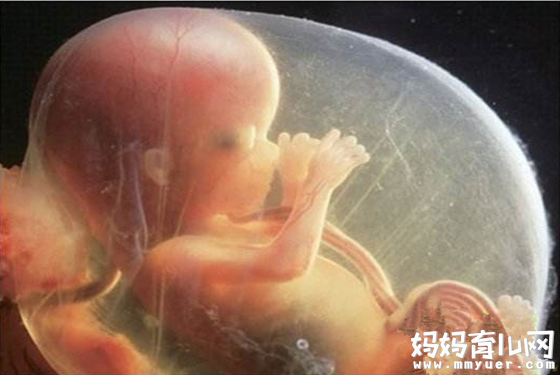

怀孕28周胎儿真实图片

28周的胎儿现在坐高约26厘米,身长约37.6厘米,体重超过900 克。

这周的胎儿可以睁开眼睛了!他的睫毛也已经完全长出来了,他的脂肪还在累积,为出生后在妈妈子宫外的生活做准备。

现在的宝宝几乎占满了整个子宫,随着空间越来越小,胎动也在减弱。但假如把手放在你的腹部,可以感觉到胎儿的活动。他可能会用小手、小脚在你的肚子里又踢又打,有时还会让自己翻个身,把你的肚子顶得一会儿这里鼓起来一会儿那里又鼓起来,也有的胎儿相对比较安静,胎儿的性格在此时已有所显现。